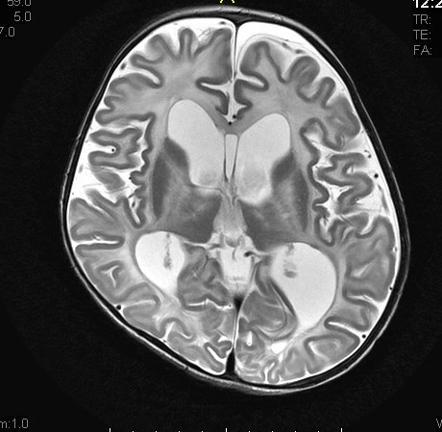

Diagnosis?

Dandy-Walker.

Hish insertion of the tentorium and cystic dilation of the 4th ventricle (fills nearly entire posterior fossa), enlarged posterior fossa, varying degrees of cerebellar vermis agenesis or hypogenesis.

Mega cisterna magna- enlargement of the cisterna magna and posterior fossa without abnormality in the 4th ventricle or vermis.

Arachnoid cyst- 4th ventricle and vermis are normal but displaced by the cyst.